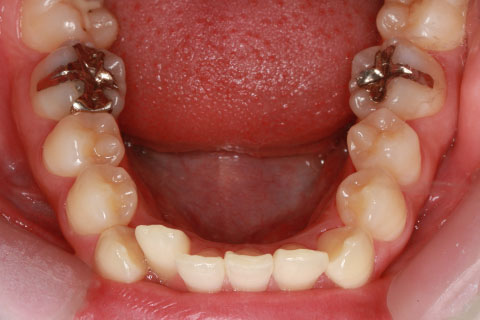

ハーフリンガル矯正3:上の歯のみ舌側矯正で治療(矯正期間24ヶ月)

治療前

治療中(開始直後)

治療中(開始半年後)

治療後

- 年齢・性別

- 25歳女性

- 治療期間

- 2年0ヶ月

- 抜歯

- 上下4番抜歯

- 治療費

- 110万円

- 治療内容

- 施術の副作用(リスク)

- 表側矯正と比較して、力学的な操作性が複雑なため、ボーイングエフェクトを起こしやすい。